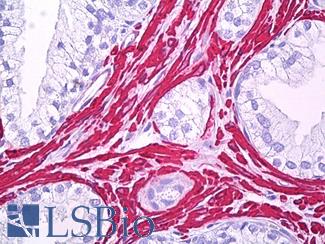

Smooth Muscle Actin (SMA / ACTA2)

Anti-Smooth Muscle Actin antibody IHC of human prostate, smooth muscle. Immunohistochemistry of formalin-fixed, paraffin-embedded tissue after heat-induced antigen retrieval. Antibody LS-B7351 dilution 1:50.